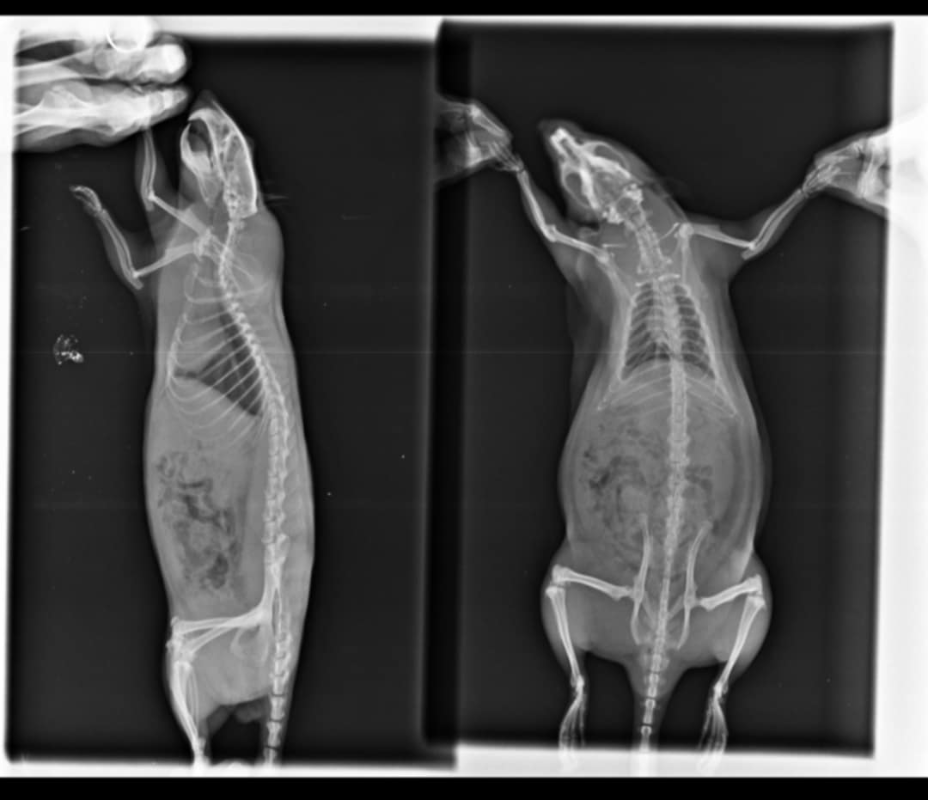

Je mets les radios, Mathilde n'arrive pas à les charger:

Radio du 5 mai:

Les radios sont pas terribles, pas très bien exposées ni assez centrées sur la cage thoracique et floues, du coup perso j'arrive pas à voir grand chose >< Mais bon tes vétos ont sans doute davantage l'habitude. Par contre je trouve aussi que le cœur est gros.